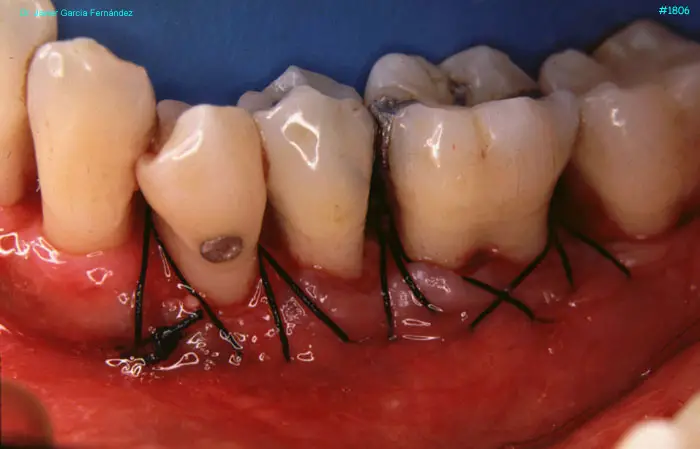

image 72